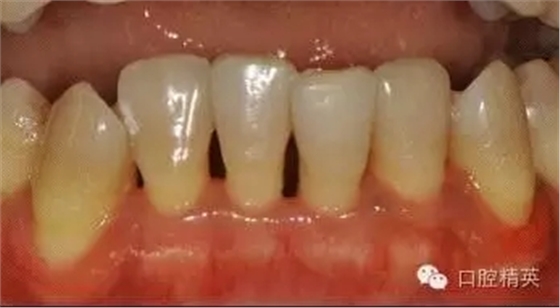

本病例 :女 34歲,主訴刷牙出血,覺(jué)牙齒輕度松動(dòng)一年。

檢查見(jiàn)大量齦上及齦下結(jié)石,探診出血,牙周袋較深,32-42 II度松動(dòng)。X線片顯示牙槽骨水平吸收。

診斷:成人慢性廣泛性中度牙周炎。

治療計(jì)劃:口腔衛(wèi)生宣教,刷牙指導(dǎo),齦上潔治,齦下刮治術(shù),下頜牙33-43牙周固定。

治療前: